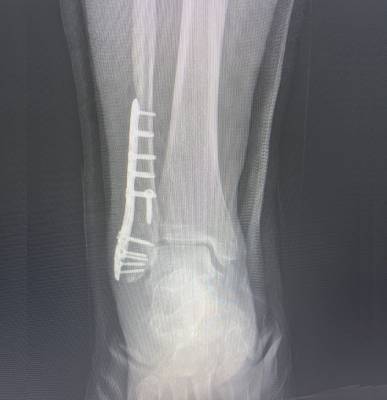

Dr. Haytham Elkhatib is a distinguished orthopaedic surgeon specializing in comprehensive musculoskeletal care. With expertise in trauma, fracture treatment, and advanced interventional joint injections, he offers innovative solutions for various conditions.

I had surgery with Dr. Haytham, and I’m very happy with the results. He previously operated on my leg after a fracture, and that surgery was very successful. Recently, I had another surgery on my knee, which was done in the simplest and most professional way. After the operation, I was able to return to my normal life — I can play football and be active again after a long time of not being able to. Dr. Haytham and his team took great care of me throughout the process, and I truly thank him for his excellent work and dedication